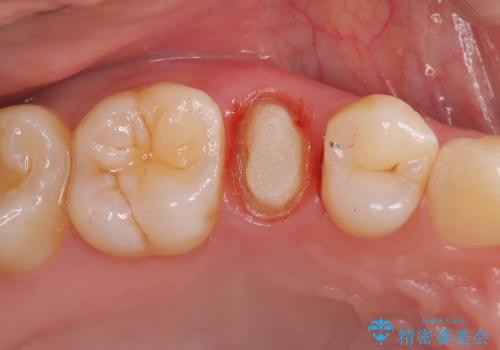

右上5番目の歯が根管治療途中となっており、前医院にて根管が狭く治療が難しいと言われてしまいセカンドオピニオンで当院にいらっしゃいました。

精密根管治療を行うこととしました。

右上5番レントゲン写真上では根管が確認しずらく、根管の狭窄が予想されました。マイクロスコープを使用し、根尖部まで器具を到達させ十分根管洗浄を行うことができました。